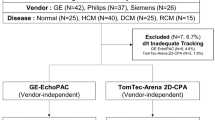

Fifteen healthy volunteers with no history of cardiovascular diseases or contraindications against MRI [16] were prospectively identified and recruited for the study after obtaining a written informed consent. The study was approved by the Ethics Committee of the Charité-University-Medicine in Berlin and complied with the Declaration of Helsinki. It was registered at the German Register for Clinical Studies (DRKS) (registration number: 00013253) and the World Health Organization (WHO) (universal trial number (UTN): U1111-1207-5874).

fSENC-image acquisitions of the gel-phantoms were repeated several times. Mean strain and standard deviation were − 28.1% (± 0.3) for the system used at site I, − 23.7 (± 0.9) for the system used at site II and − 26.8 (± 1.4) for the system used at site III. Table 1 portrays the baseline characteristics of the volunteers, vital signs and median (IQR) strain values. One complete fSENC-examination including all images was acquired in a median (IQR) scan time of two (1–4) min at all sites. Median image analysis time ranged from 10 to 14 min for one whole examination. A total of four scans were performed for each volunteer (twice before and twice after the break). At site I, one scan had to be excluded from GLS-analysis owing to motion artifacts during acquisition of the short-axis images. At site II, one volunteer could not be scanned due to unexpected technical difficulties. Further four scans were excluded from GLS- and nine from GCS-analysis because of artifacts that would not allow reliable contouring of the heart. At site III, no scan was excluded. A total of 51 scans (85.0%) were left for GLS-and 47 scans (78.3%) for GCS-analysis.